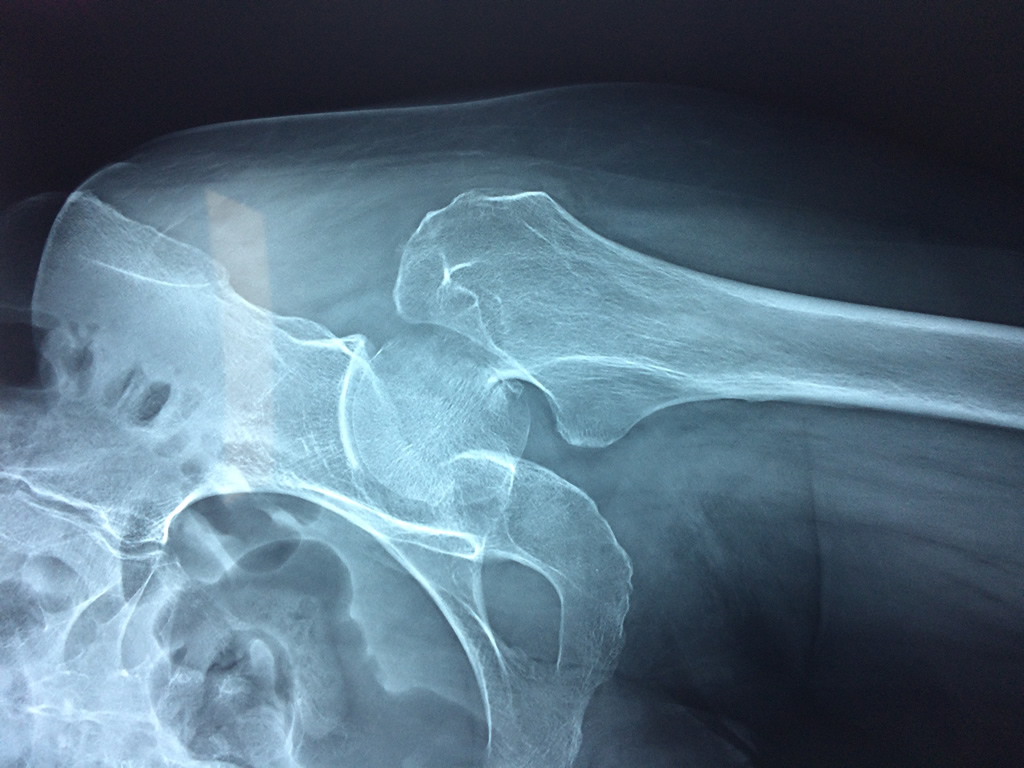

Clavícula